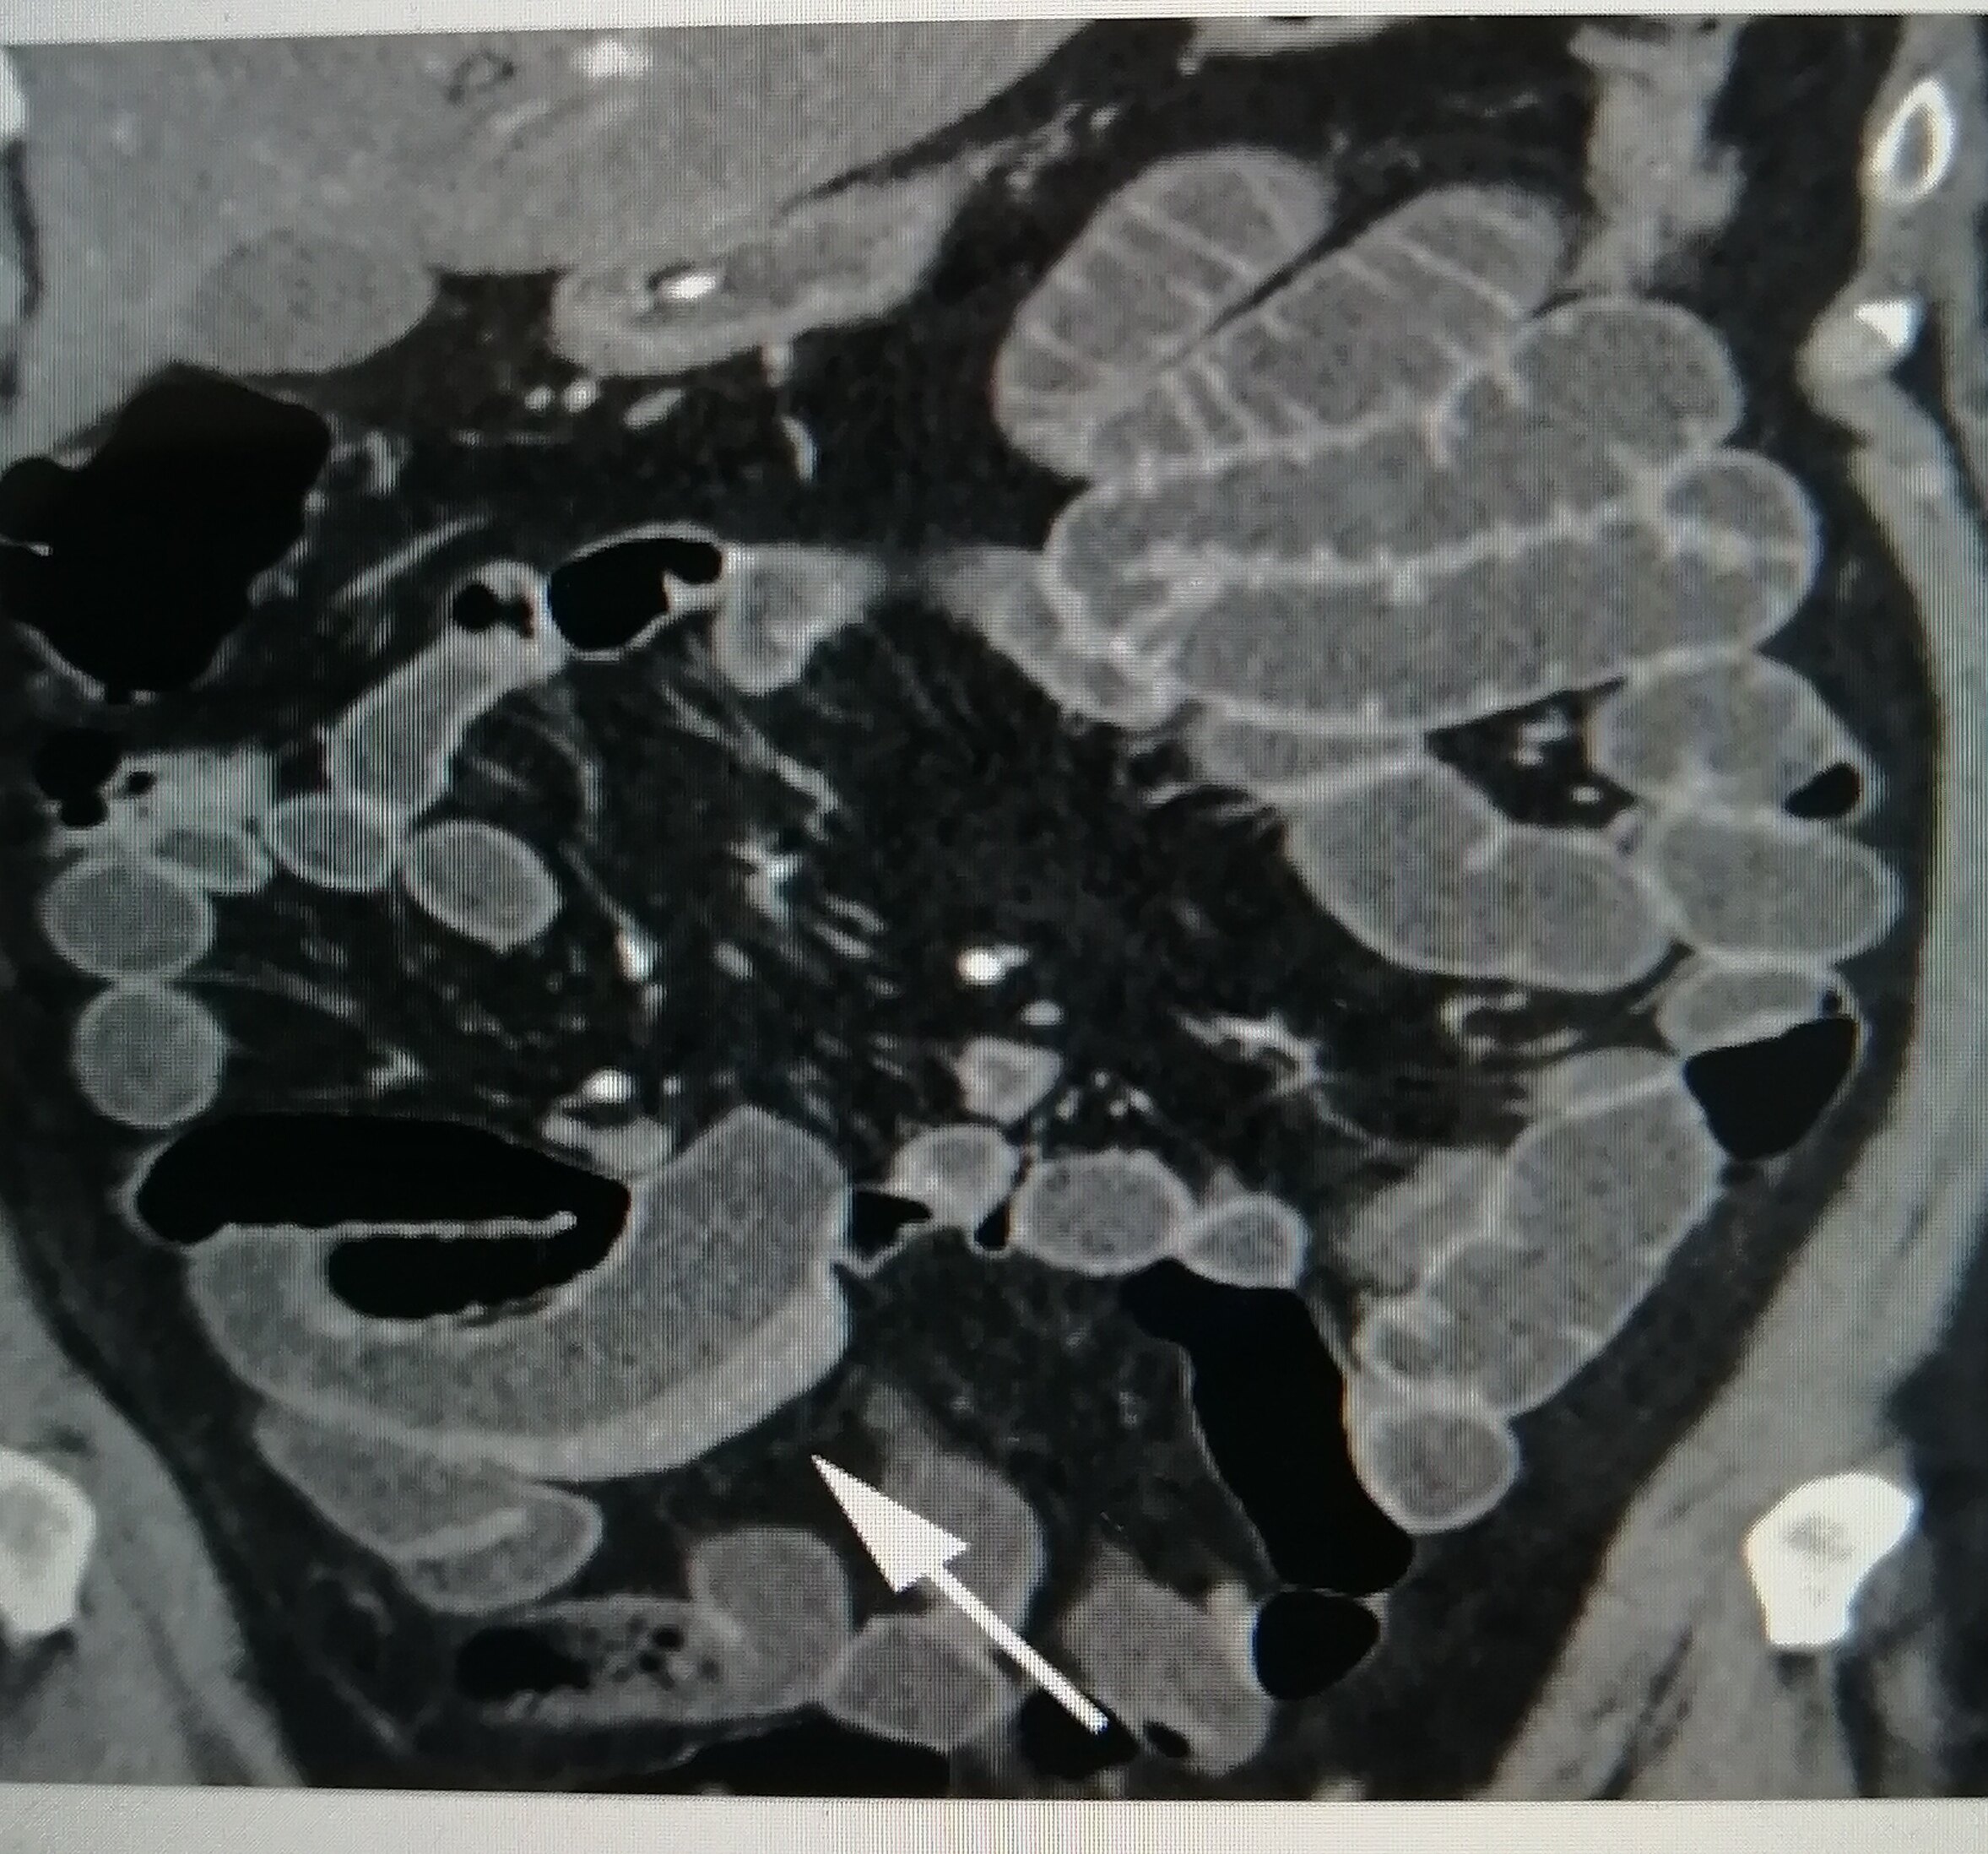

哎呀,说到克罗恩病在肠镜下的表现,那真是一场让人心疼的景象。想象一下,那些平时默默工作的肠道,突然间变得像是经历了战火的废墟。肠壁上,那些原本光滑柔软的地方,现在却布满了溃疡,就像是大地被无情地撕裂开来。

这些溃疡,有的深,有的浅,有的还在不停地渗出液体,就像是伤口在不停地哭泣。更让人揪心的是,这些伤口之间,还夹杂着一些狭窄的区域,肠道在这些地方被挤压得几乎要窒息。这不禁让人想到,肠道在无声地呼救,希望能有人听到它的痛苦。